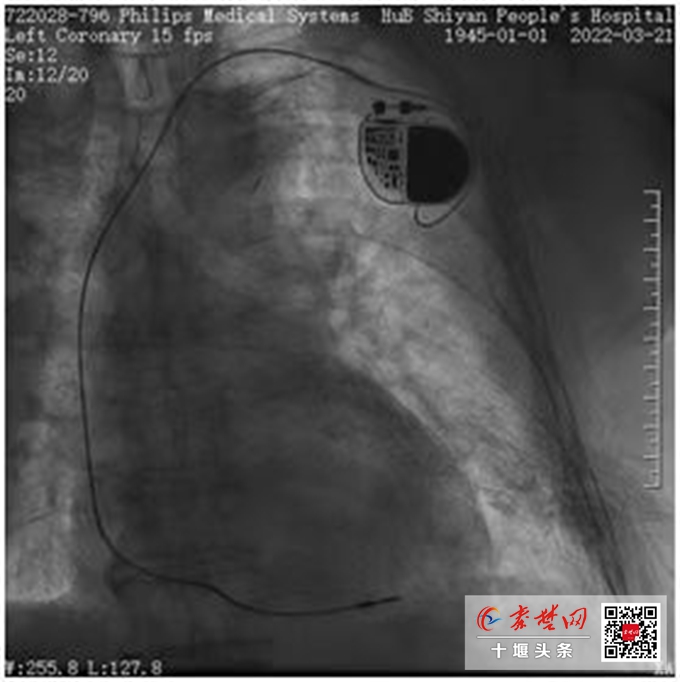

传统起搏器由脉冲发生器和电极导线组成(造影效果)

“传统的起搏器由脉冲发生器和电极导线组成,电极导线长度约52-60cm。脉冲发生器发放由电池提供能量的电脉冲,通过导线的传导,刺激电极所接触的心肌,使心脏激动和收缩,达到治疗疾病的目的。”张友恩介绍,安装传统起搏器时,医生需要在患者皮下组织和胸大肌之间分离出一个囊袋,将起搏器埋藏在皮下的囊袋里。“要切开胸部皮肤,存在手术创伤大、伤口愈合慢、感染风险相对高、术后恢复慢等风险,对于高奶奶这样基础疾病多,体质孱弱的患者而言,并不适用。”张友恩表示。